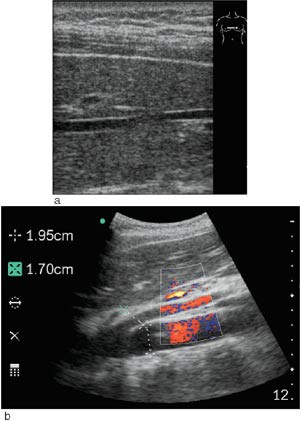

Undersøkerens totale tilfredshet med bruk av denne skanneren var: 0 lite tilfreds, 8 % litt tilfreds, 11 % moderat tilfreds, 36 % meget tilfreds, 45 % svært tilfreds. Skanneren var ikke bare egnet til «enkle» problemstillinger, men kunne også gi tilfredsstillende svar på mer kompliserte kliniske og bildemessige utfordringer (fig 3, fig 4).

I 81 % av tilfellene fant vi tilfredsstillende bildekvalitet (e-fig 1) med bruk av mobil skanner, til tross for at det hos 28 % av pasientene var dårlig innsyn. Noen syntes at skjermen var for liten og at dette utgjorde en begrensende faktor. Et ultrasonogram hvor man sammenlikner opptak gjort på samme pasienter med Sonosite 180 mot Siemens Elegra demonstrerer hvor bra bildekvaliteten er (fig 2). Gjennomsnittlig tidsbruk under skanning var 7 ± 3 minutter. I 83 % av tilfellene ble den aktuelle kliniske problemstillingen adekvat besvart med mobil skanning, i fire tilfeller (11 %) ble det ansett som nyttig å skanne pasienten med et stasjonært ultralydapparat i tillegg. Utredning og/eller behandling av pasientene ble i 39 % av tilfellene endret som følge av skanning.

Skanning med mobilultralyd førte til at man unnlot å henvise til ordinær ultralydundersøkelse ved røntgenavdelingen i 64 % av tilfellene. I fem av 36 tilfeller (14 %) ble pasienten utredet videre med andre radiologiske metoder og i fem tilfeller med endoskopi for å avklare diagnosen. Den ultrasonografiske diagnosen ble hos 90 % av pasientene bekreftet i ettertid ved gjennomgang av journaler og radiologiske bilder.